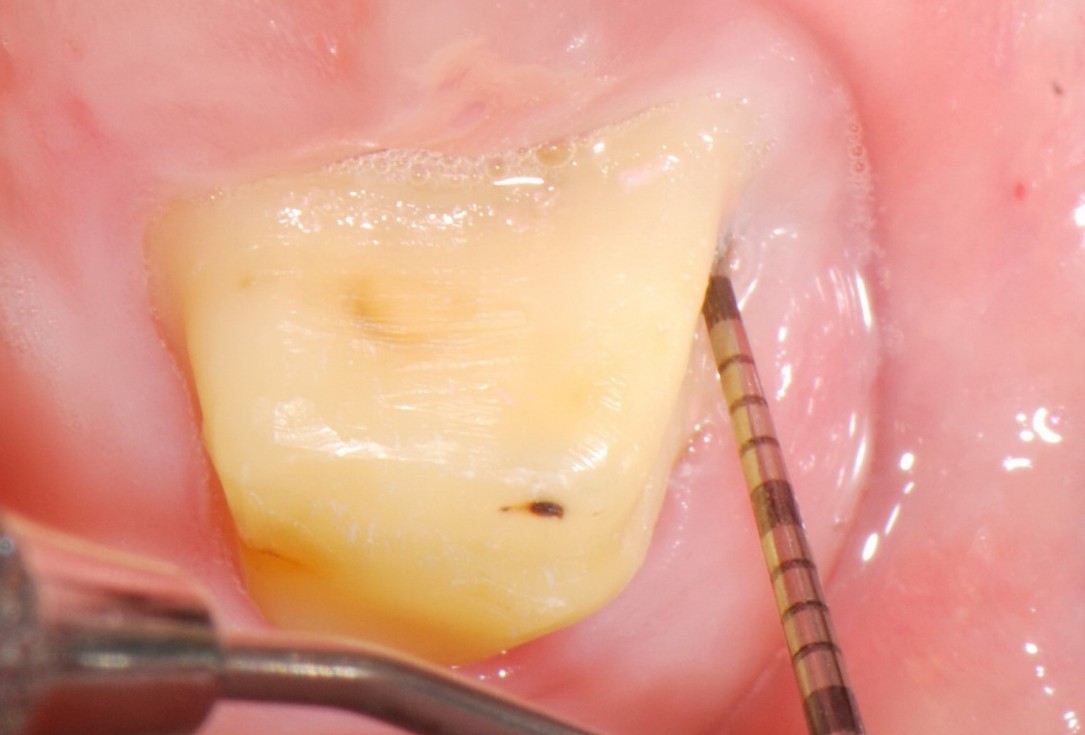

02/06 - Pre-surgical probing.Treatment of a periodontal bone defect adjacent to an edentulous site using Straumann® Emdogain® - Prof. Dr. P. Windisch

Radiographic view before periodontal regenerative therapy with Straumann® Emdogain®. A deep intrabony defect appeared mesially and distally on the left mandibular first premolar. Pre-surgical probing measured 8 mm. The defect morphology presented as well-contained.